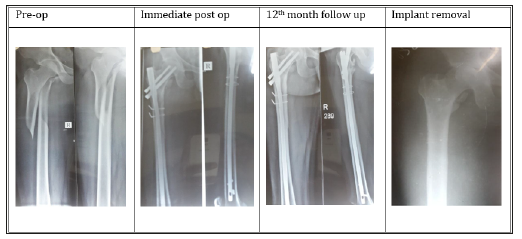

Follow up: Tablet Risedronate 35mg once weekly for 12weeks were given to improve the bone mineral density in patients with severe degree osteoporosis. All the patients were advised to completely weight bearing after 10-12 weeks of post-operative period. All patients were followed up at the end of 1,2,6,12 and 18 months. At each follow up, the radiographs of upper femur and hip were taken to assess the fracture union and the complications. The functional results were calculated according to Harris hip score. All patients enrolled in the study were offered with surgical implant removal at an average of 18months post-surgical procedure who showed the clinical and the radiological union of fractures and improved functional quality of life (Figures 5 & 6).

Figure 5:Trochanteric fracture fixed with proximal femoral nail.